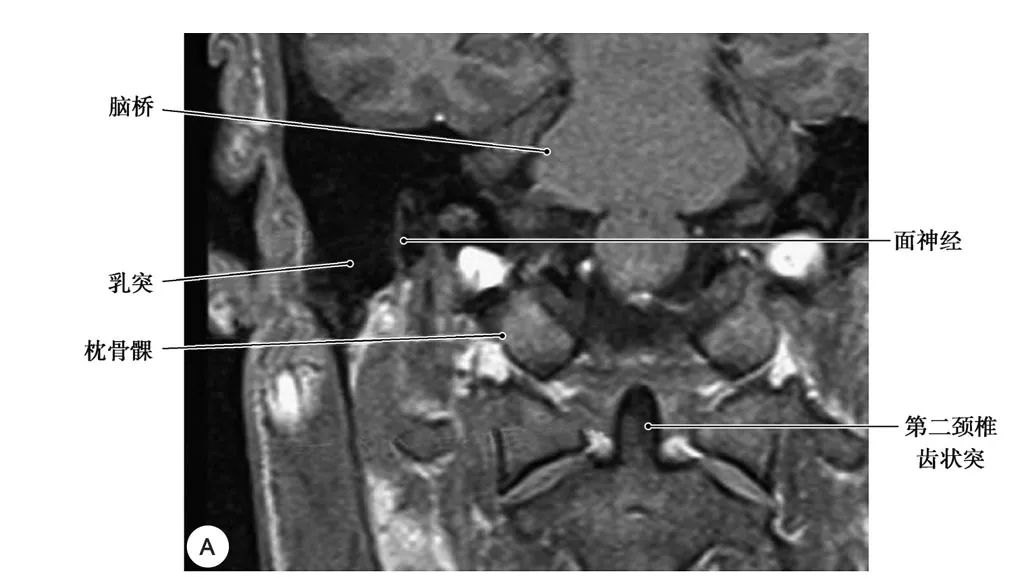

(MRI冠状面)

面神经乳突段及其周围结构